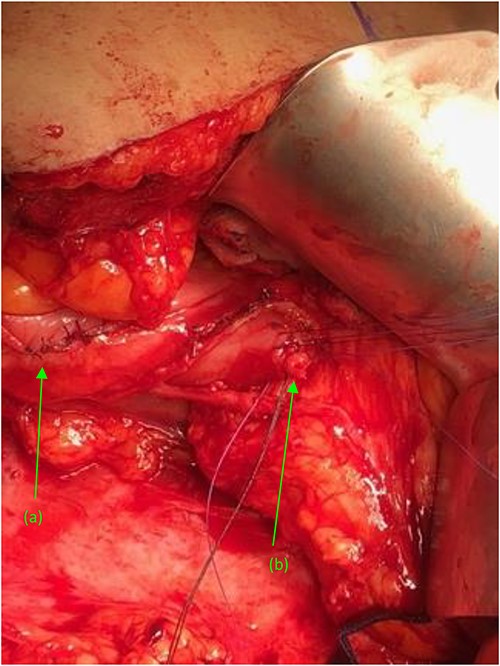

Right kidney, status post nephrectomy, transected at the renal hilum. (a) First fistulous tract exiting the renal pelvis. (b) Second fistulous tract extending from its origin point off the proximal ureter and branching just distal to the ureters entry at the renal pelvis.

Attention was turned back to the fistulous connections at their duodenal entry points (Fig. 4). Both fistulas, were trimmed to their base, debrided, and primarily closed using 3-0 Vicryl sutures in an interrupted fashion. Interrupted 3-0 Vicryl sutures were then used to Lambert the repaired 2nd and 3rd portions of the duodenum (Fig. 5). Acti-seal sealant was sprayed atop the repairs, and Gerota’s was laid atop. Surgicel was then placed in the raw, inflamed posterior space of the fossa and adequate hemostasis was achieved. A 19 French Blake drain was brought through an inferior skin incision, laid in the renal fossa adjacent to the duodenal repairs, and sutured in place. The abdomen was then closed in the standard fashion, with individual suture closure of the fascia, internal and external oblique muscles and skin layers.